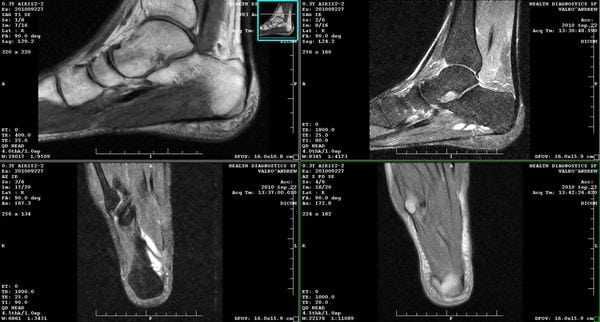

2. МРТ при эндопротезе и артродезе мелких суставов кисти, стопы:

• Силиконовые импланты имеют низкий сигнал во всех последовательностях МРТ

• Перелом протеза:

о Переломы лучше визуализируются, чем на рентгенограмме

о Мелкие фрагменты визуализируются на фоне скопления жидкости

• Болезнь частиц:

о Синовит:

- Низкая интенсивность сигнала в Т1, высокий сигнал от жидкости в T2

- Утолщенная синовиальная оболочка

о Отек костного мозга, остеолиз:

- Низкая интенсивность сигнала в Т1, высокая интенсивность сигнала в режиме T2 в костном мозге и кистах

о МРТ позволяет визуализировать распространенность синовита и костной деструкции

(Справа) Фронтальное Т1ВИ МР-И большого пальца кисти, этот же случай: перелом остаточного фланга треугольной формы импланта кости-трапеции, расположенною в основании первой пястной кости. (Слева) Фронтальное Т2 FS МР-И, этот же случай: синовит округлой формы с высоким сигналом вокруг остеолитических кист оснований второй и третьей костей пясти, а также трапециевидной, головчатой и крючковидной костей. Синовит/остеолиз в этом случае массивный.